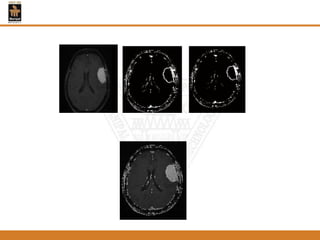

Figure 2: Alevel set segmentation